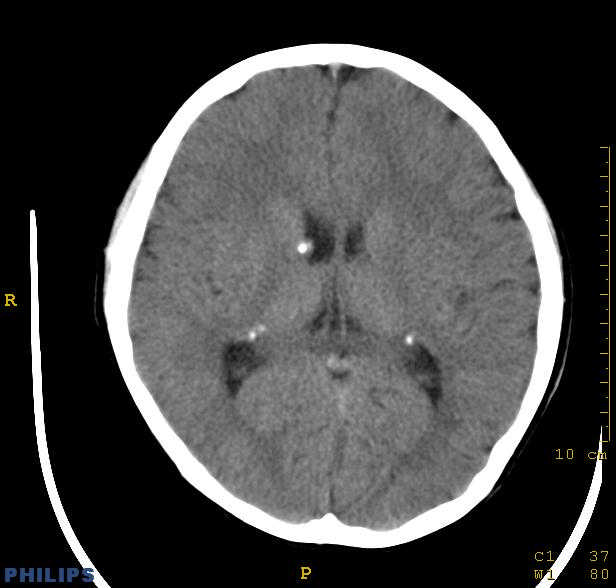

标题: PED0043:头颅平扫 男12岁.典型结节性硬化 [打印本页]

标题: PED0043:头颅平扫 男12岁.典型结节性硬化

典型结节性硬化

[病因病理]

结节硬化是常染色体显性遗传缺陷或基因突变引起的疾病,脑部病理可见神经胶质增生性硬化结节,位于大脑皮质、基底核及侧脑室壁的室管膜下。结节质地较硬,多有钙化。室管膜下结节可演变为巨细胞星形细胞瘤,亦可发生皮质错构瘤,常合并有其他器官畸形和肿瘤。

[影像学表现]

1.ct表现:

①室管膜下有多发性小结节状钙化影,也可为单发、不强化;小结节亦可未钙化;突入脑室可以强化;但有钙化者居多,颅内异常钙化高达90%。一般出生后2年即呈典型钙化。

②10%-15%的病例可能恶变为室管膜下巨细胞星形细胞瘤或其他胶质瘤。前者常位于室间孔附近,生长缓慢,增强扫描可产生异常强化。

③可见白质区脱髓鞘的低密度区。

④可伴脑灰质异位。

⑤脑室扩大系阻塞性脑积水或脑发育不良所致。